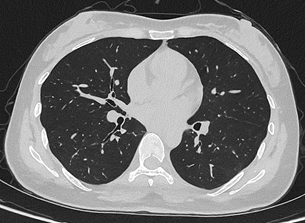

联影uCT Ultima扫描的0.2mm肺部超高清成像,扫描剂量低至0.1mSv

目前,华西厦门医院已基于该设备完成第一批患者扫描。华西厦门医院党委书记廖志林表示,光子计数能谱CT的临床落地实现了对国外“卡脖子”技术的突破,大幅降低了辐射剂量,日本精品高清一区二区_女人被添全过程A片让患者CT扫描更安全。临床案例显示,设备在低剂量条件下仍可实现肺结节的高清成像,临床价值突出。该设备将在医院的全链条、全生命周期健康管理服务中发挥重要作用。